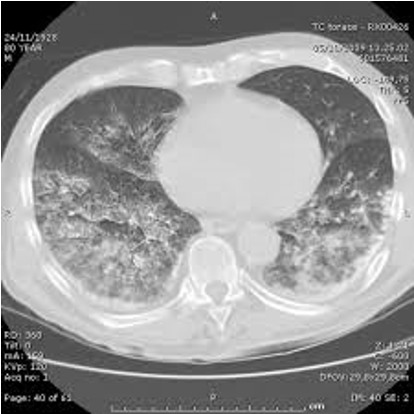

Pulmonary edema due to aspiration of gastrografin